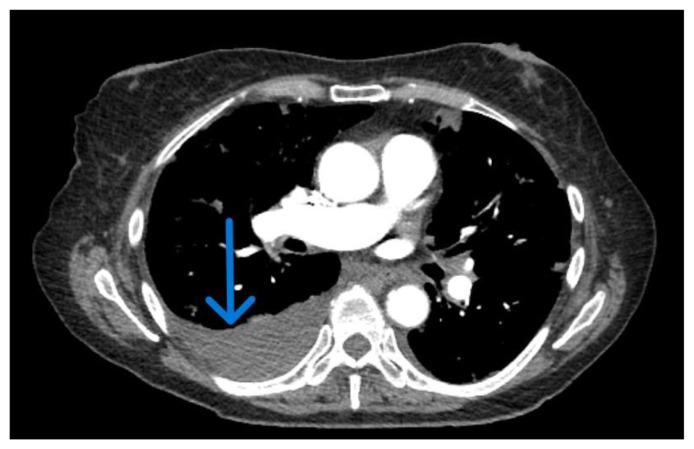

In the landscape of pancreatic cancer, extra-pancreatic manifestations like pleural effusion are infrequent. Our case spotlights a 78-year-old female with a recent diagnosis of pancreatic adenocarcinoma with isolated metastasis to the pleura. The patient presented with exacerbated dyspnea and cough, shedding light on the uncommon link between pancreatic adenocarcinoma and pleural effusion. Pancreatic cancer typically exhibits nonspecific symptoms, and its association with pleural effusion significantly complicates diagnosis, often leading to delayed recognition and management challenges. This case underscores the diagnostic complexities and the need for heightened vigilance when faced with atypical presentations in pancreatic cancer, emphasizing the intricacies of managing such rare extra-pancreatic manifestations.